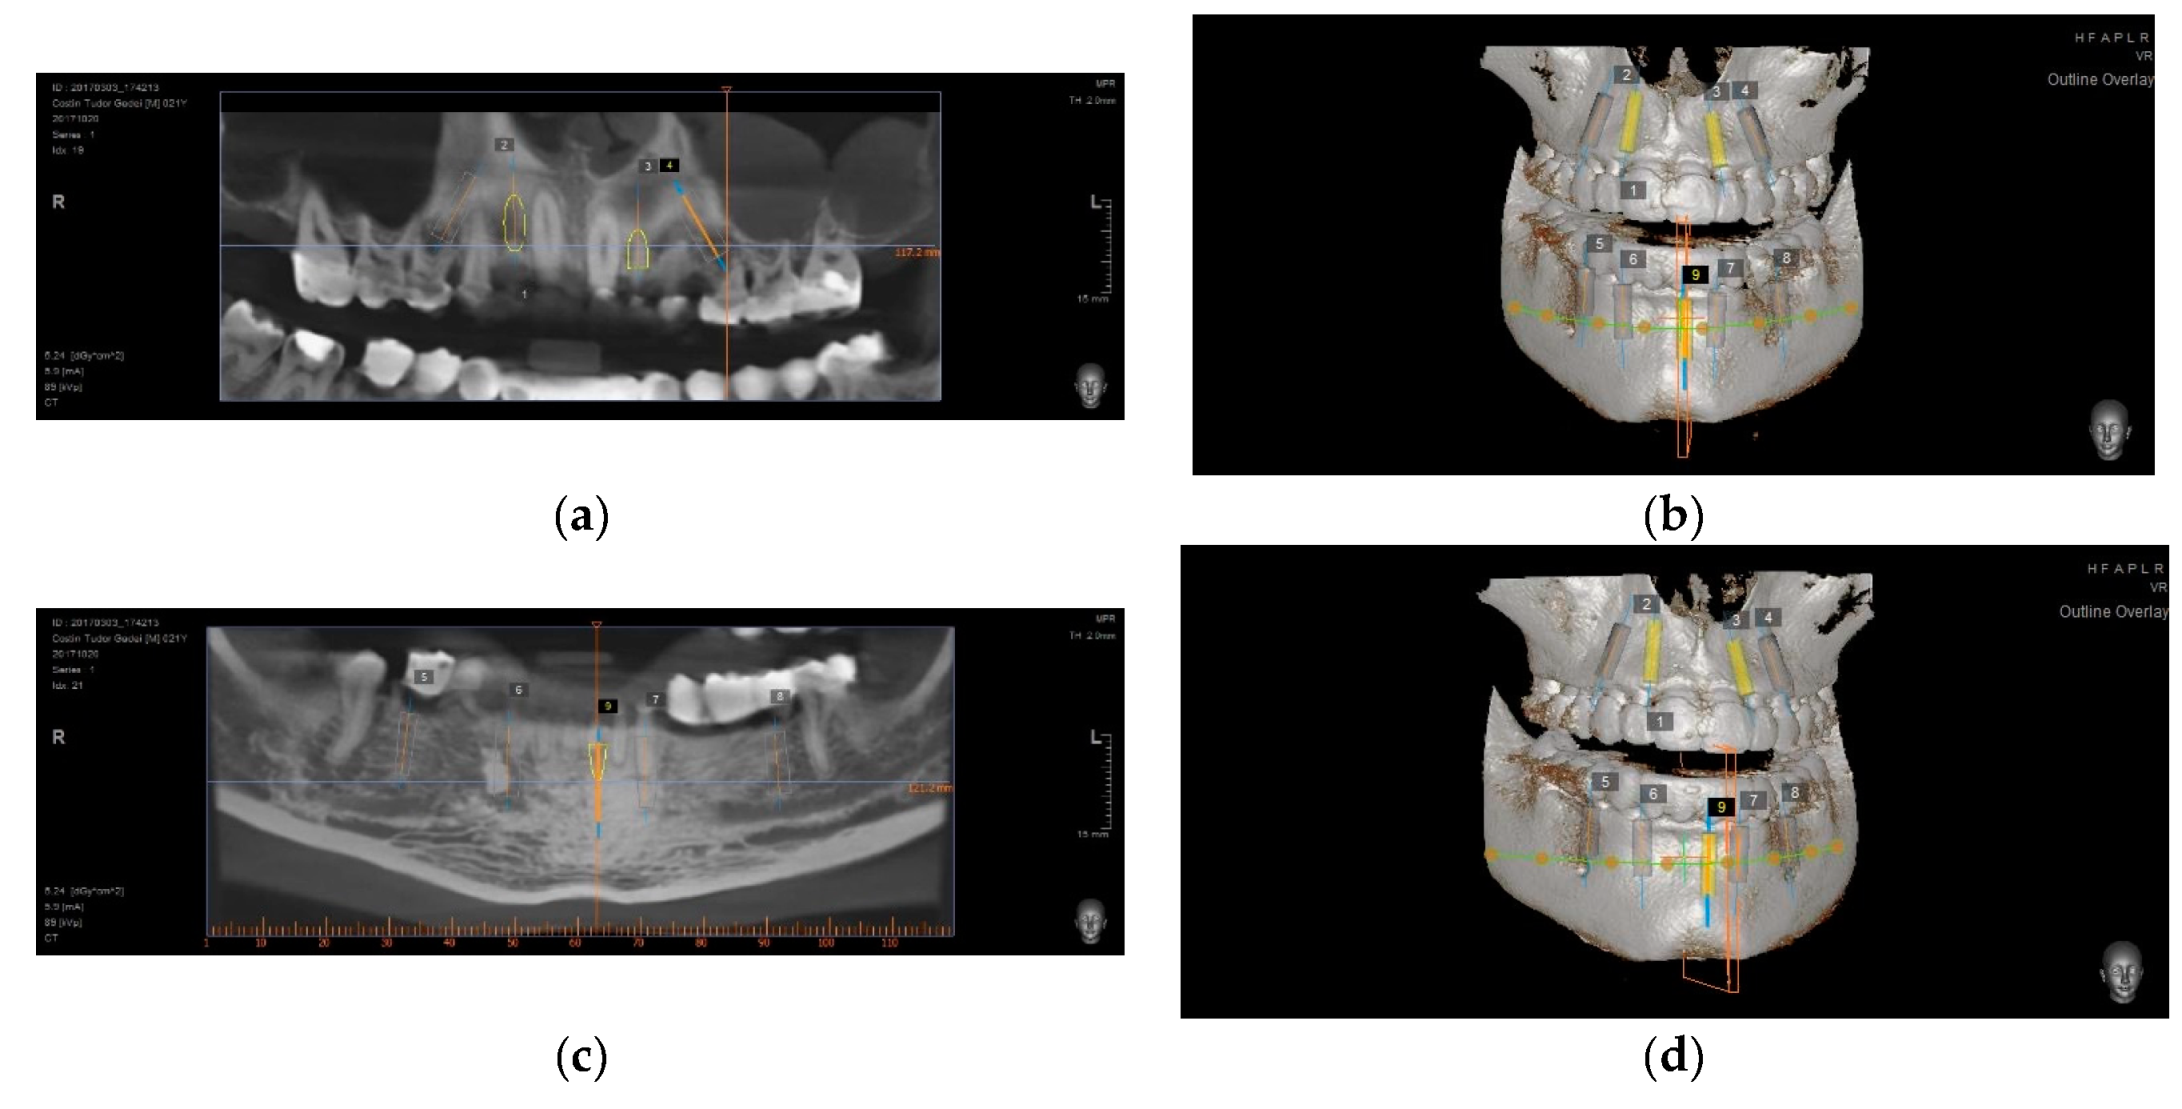

- Upper and lower implant placement with provisional restorations